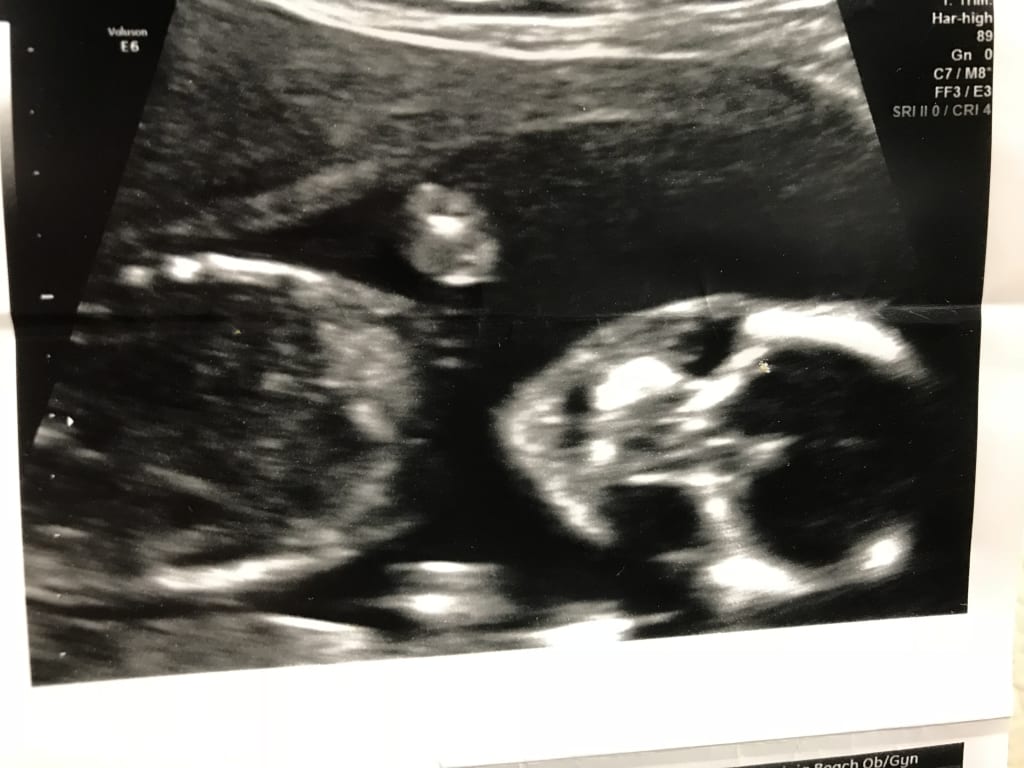

PROBLEM! At my first appointment they found a lesion on her lung. After 10 weeks of monitoring, it has grown larger. It needs to be removed to prevent it from becoming deformed.

At 31 weeks, it will be decided when to perform surgery at CHKD. An ultrasound will be done to determine if she can be born at 34-35 weeks. Ultimately, the baby will be brought prematurely into this world. She will, soon after birth, undergo surgery to remove the lesion from her lung. If it appears to interfere with development, she will arrive as early as 32 weeks. Currently, I am on strict bed rest as she has already "dropped." I just got a job but had to go on leave without pay per doctor's instructions. Physical labor is out of the question as there is a concern to keep the plug intact and for her to "stay put." I am following doctors orders! Surgery is scary and risky! As a newborn and due to this type of surgery, her risk of complication is much greater than average. This is what pediatrics has shared. The current and continued lost wages due to the temporary inability to work (I don’t qualify for FMLA & have no accrued paid leave), additional appointments to specialists, travel expenses and many other costs that have and will be incurred are growing. There are many uncertainties and this page was created to help relieve a small portion of the financial burden of this ordeal so as to focus on the baby’s growing strong. Ideally, she will have surgery after she is full term. This is possible but surgery is inevitable.